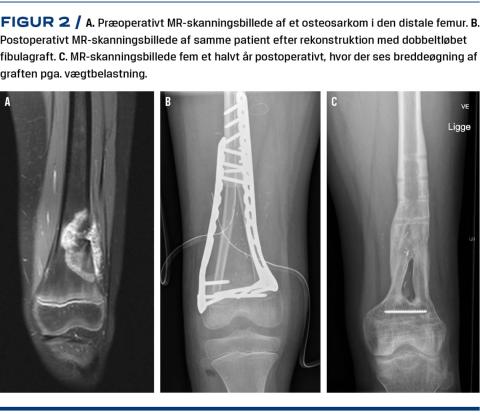

Knogletransport

Ved substantielle knogledefekter, hvor det ikke er muligt at foretage rekonstruktion med fibulagraft, kan der i stedet foretages knogletransport, også kaldet distraktionsosteogenese. Til knogletransport anvendes ringfiksatorer med ilizarovapparatur (Figur 3) eller forlængelsesmarvsøm. I begge metoder udnyttes princippet om, at når to knogleender kontinuerligt trækkes fra hinanden, vil ny knogle dannes i spalten mellem disse og over tid konsolidere til normal knogle [18]. Ved anvendelse af ringfiksatorer foretages forlængelsen typisk ambulant. Det er en langvarig behandlingsmetode, og som tommelfingerregel tager det en måned at forlænge knoglen 1 cm. De motoriserede marvsøm, der drives af en ekstern elektromagnet, kan betjenes i hjemmet af patienten og forældrene og minimerer risikoen for infektion i modsætning til ringfiksatoren, hvor der er en betydelig risiko for infektion omkring pinhullerne.

Knogletransport anvendes især til rekonstruktion ved lavmaligne knogletumorer, hyppigst adamantinomer, hvor der ofte foretages omfattende excision [5]. I et tidligere studie [19] har man undersøgt tiårsopfølgning hos ni pædiatriske patienter, der havde knogletumorer i en underekstremitet og blev behandlet med knogletransport. I gennemsnit blev der anvendt ekstern fiksering i 368 dage med en variation på 124-496 dage. Den gennemsnitlige MSTS-score var 29. En patient fik dyb infektion og måtte revideres, og tre havde forsinket knogleheling.